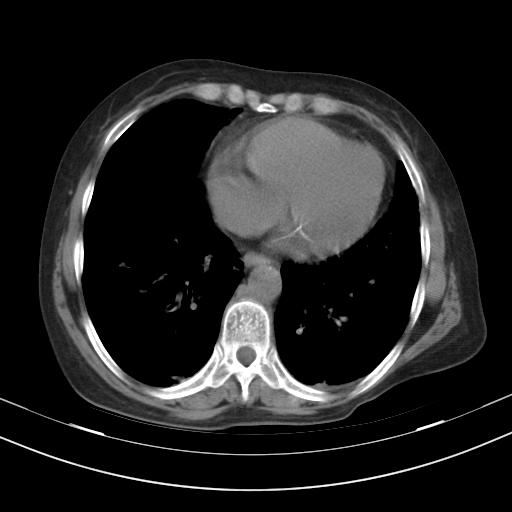

老年女性,嗜睡3天,意识模糊。轻咳,无发热。

两肺慢支炎伴感染,左侧胸腔积液。纵膈及双侧肺门淋巴结肿大建议复查。

双肺多发淡片影,毛玻璃影,,支持支气管肺炎,,建议血气找原因,,嗜睡是否肺性脑病?有没有慢支病史?

双肺炎症,建议抗炎治疗后复查,见过几个老年肺炎病例,没有发烧、咳嗽症状,直接以昏迷就诊。

1)两肺感染性病变;建议抗炎治疗后复查。2)纵隔淋巴结肿大。3)左侧胸腔积液。